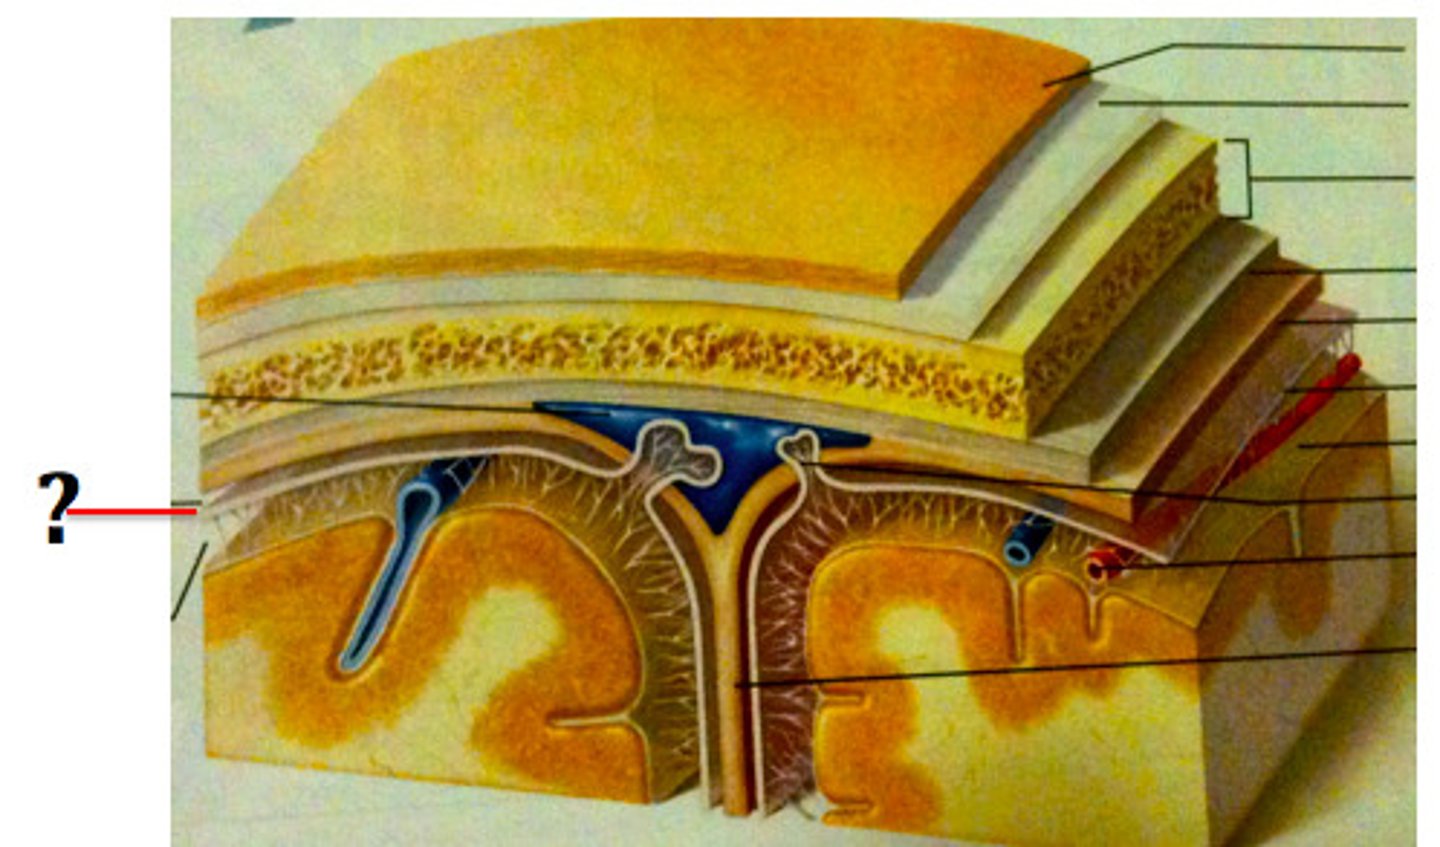

arachnoid mater

middle meninge, collagen and elastin fiber, spider web look

subarachnoid space

filled with cerebrospinal fluid

subdural space

below the dura mater

potential space (if you have a head injury

the blood goes into the subdural space)